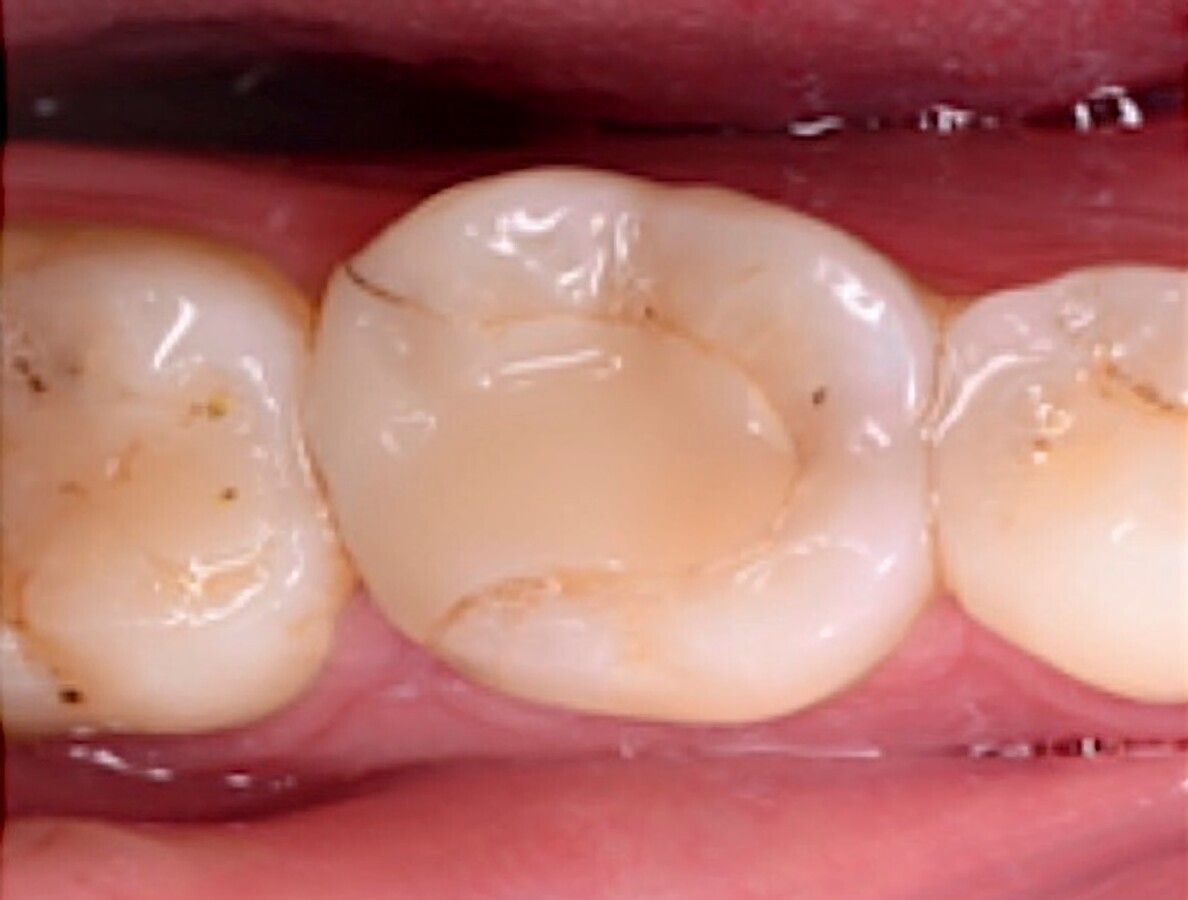

Fig. 3. Imagen clínica inicial del diente 3.6.